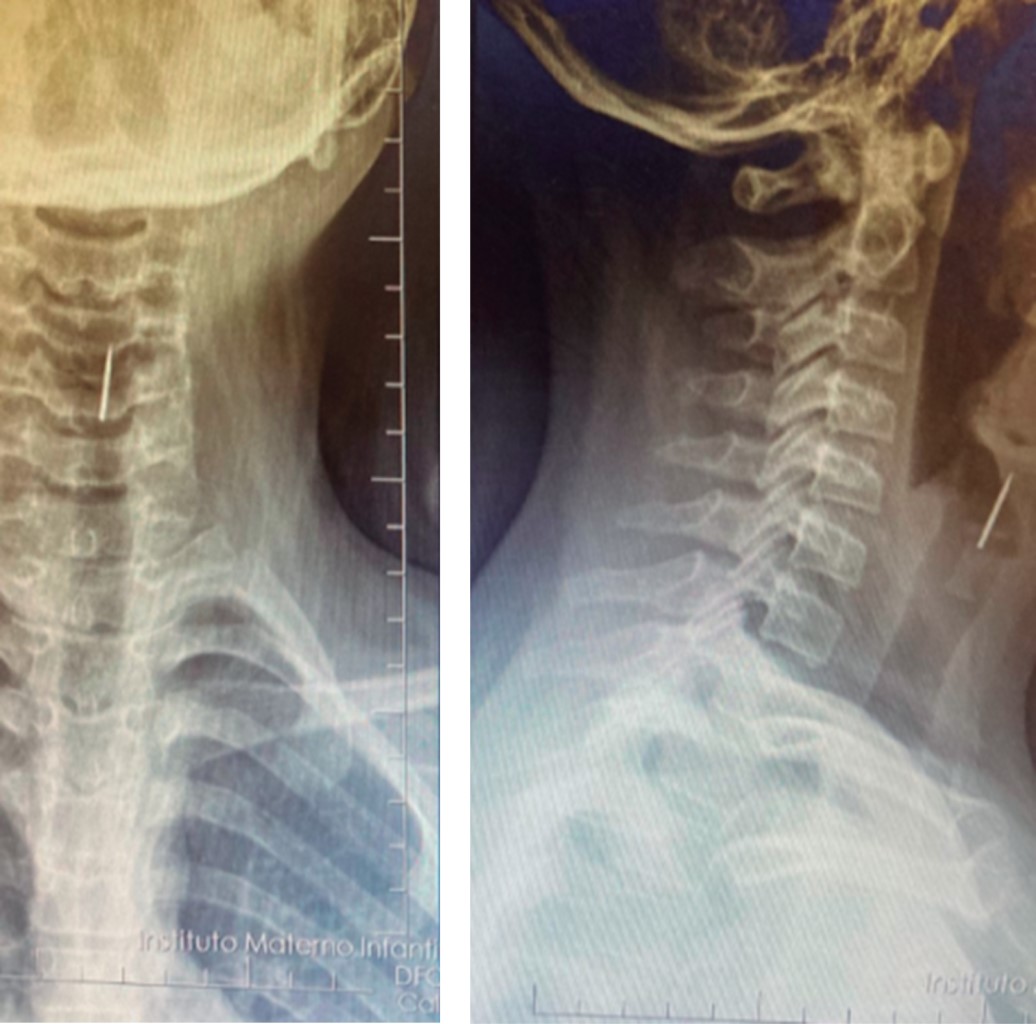

La radiografía de tórax es un estudio de bajo costo que debe realizarse ante la sospecha de aspiración de cuerpo extraño. La radiografía de tórax normal no excluye la presencia de un cuerpo extraño en la vía aérea. Se ha reportado 30-50% de radiografías normales de pacientes con cuerpo extraño alojados en los bronquios.9 Otras series reportan 18% de radiografías normales y 48% con hallazgos inespecíficos como hiperinsuflación o atrapamiento de aire, atelectasia, infiltrados o engrosamiento de la pared bronquial (Figuras 1, 2, 3 y 4).10

Figura 1

Figura 2

Figura 3

Figura 4